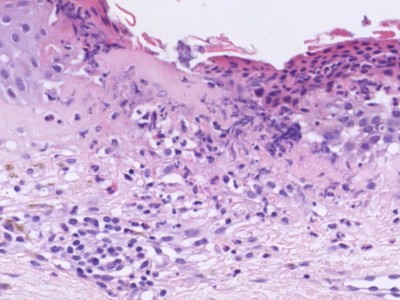

Histologie geneesmiddelreactie Histologie geneesmiddelreactie Histologie geneesmiddelreactie

ingescande coupe (zoom) ingescande coupe (zoom) ingescande coupe (zoom)

Bron hoge resolutie PA-foto's: Kevin Kwee en Afdeling Pathologie MUMC. Klik op de afbeelding om in te zoomen.

De meest voorkomende geneesmiddelenreactie is het maculeuze of maculopapuleuze exantheem, verspreid over het gehele lichaam. Dit is een goed herkenbaar klinisch beeld, hoewel er altijd andere zaken in de DD staan. De diagnose kan worden gesteld op het klinisch beeld en de anamnese (verdacht middel gegeven). Eventueel kan het bevestigd worden met een biopt, als er twijfel is. Een biopt kan geen uitsluitsel geven over welk middel het heeft veroorzaakt. Bij meerdere geneesmiddelen kan het een enorme puzzel zijn. Vaak is er alleen maar achter te komen door middelen te stoppen of te vervangen door een niet verwant middel. Let op de tijdsrelatie: 7-10 dagen voor een type III-reactie, eerder (1-5) dagen als het middel eerder is gegeven. Binnen enkele tot 30 minuten bij een type I-reactie. Enkele dagen tot enkele weken voor een type IV reactie. 1-8 weken voor een TEN. Ook middelen die jarenlang zonder problemen gebruikt zijn, kunnen opeens een toxicodermie veroorzaken (hoewel dat niet vaak voorkomt). Na het staken of vervangen van een middel moet langdurig worden afgewacht. Geneesmiddelenreacties kunnen 1-2 maanden aanhouden en soms nog langer. Het geneesmiddel is vaak al na enkele uren tot dagen volledig uit het lichaam, maar er zijn (bij type IV reacties) klonen van lymfocyten gevormd, gericht tegen een bepaald molecuul, die een reactie veroorzaken in de epidermis. Die lymfocyten hebben een bepaalde levensduur. Soms gaat een reactie helemaal niet over en een enkele keer ontstaat zelfs een maligne T-cel kloon.